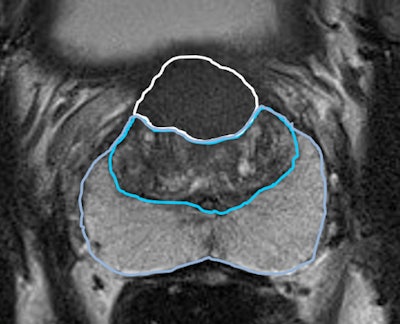

![T2-weighted image shows the prostate of a patient (age unknown) with an elevated prostate-specific antigen (PSA) level and previous negative transrectal ultrasound guided biopsies. Multiparametric MRI showed a large PI-RADS 5 lesion in the anterior part of the transition zone, which proved to be a clinically significant prostate cancer (International Society of Urologic Pathologists [ISUP] grade 3). Benign prostatic hypertrophy in the transition is visible as 'organized chaos' (blue area). All images courtesy of Prof. Jelle Barentsz, Dr. Maarten de Rooij, and Dr. Bas Israël.](https://img.auntminnieeurope.com/files/base/smg/all/image/2020/05/ame.2020_05_27_16_34_2157_2020_27_05_MRI_Insider_prostate_MRI_1.png?auto=format%2Ccompress&fit=max&q=70&w=400)